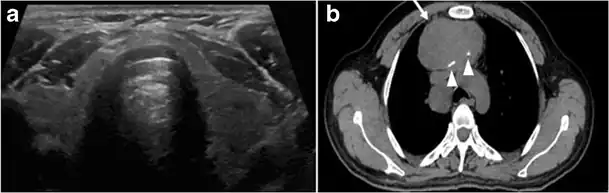

Fig. 4. A 45-year-old male patient presented with anterior mediastinal metastatic PTC lesions and occult primary on imaging. Histopathology examination of the resected thyroid gland revealed micro-foci of PTC; the largest, in the isthmus, measured 4 mm. a transverse greyscale ultrasound of the thyroid demonstrates homogeneous gland with normal echogenicity and size. No focal lesion or micro-calcifications. b Non-enhanced CT scan obtained as part of PET/CT examination shows a heterogeneous, large, relatively dense anterior mediastinal mass (white arrow) with peripheral calcification (arrowheads). Thyroid gland has normal CT appearance with no abnormal FDG uptake (not shown).[1] -